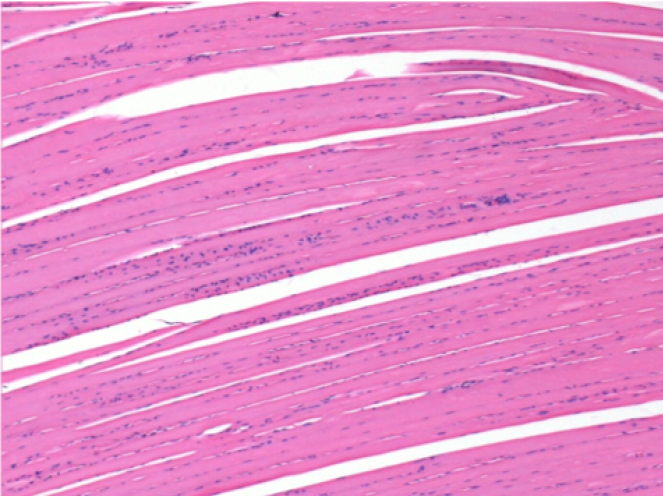

Histology

On Wistar rats

Courtesy of Lab of Pathology Department on Medicine School of Ribeirão Preto – USP

-hematoxilin-eosin

10 days after Endopeel Injection 0.1ml in the right pretibial muscle.

Here you may see the formation of the vacuoles which are surrounded by lymphocytes. Vacuoles are different from tissue necrosis . The presence of lymphocytes is related to the permeability of the cell membranes.